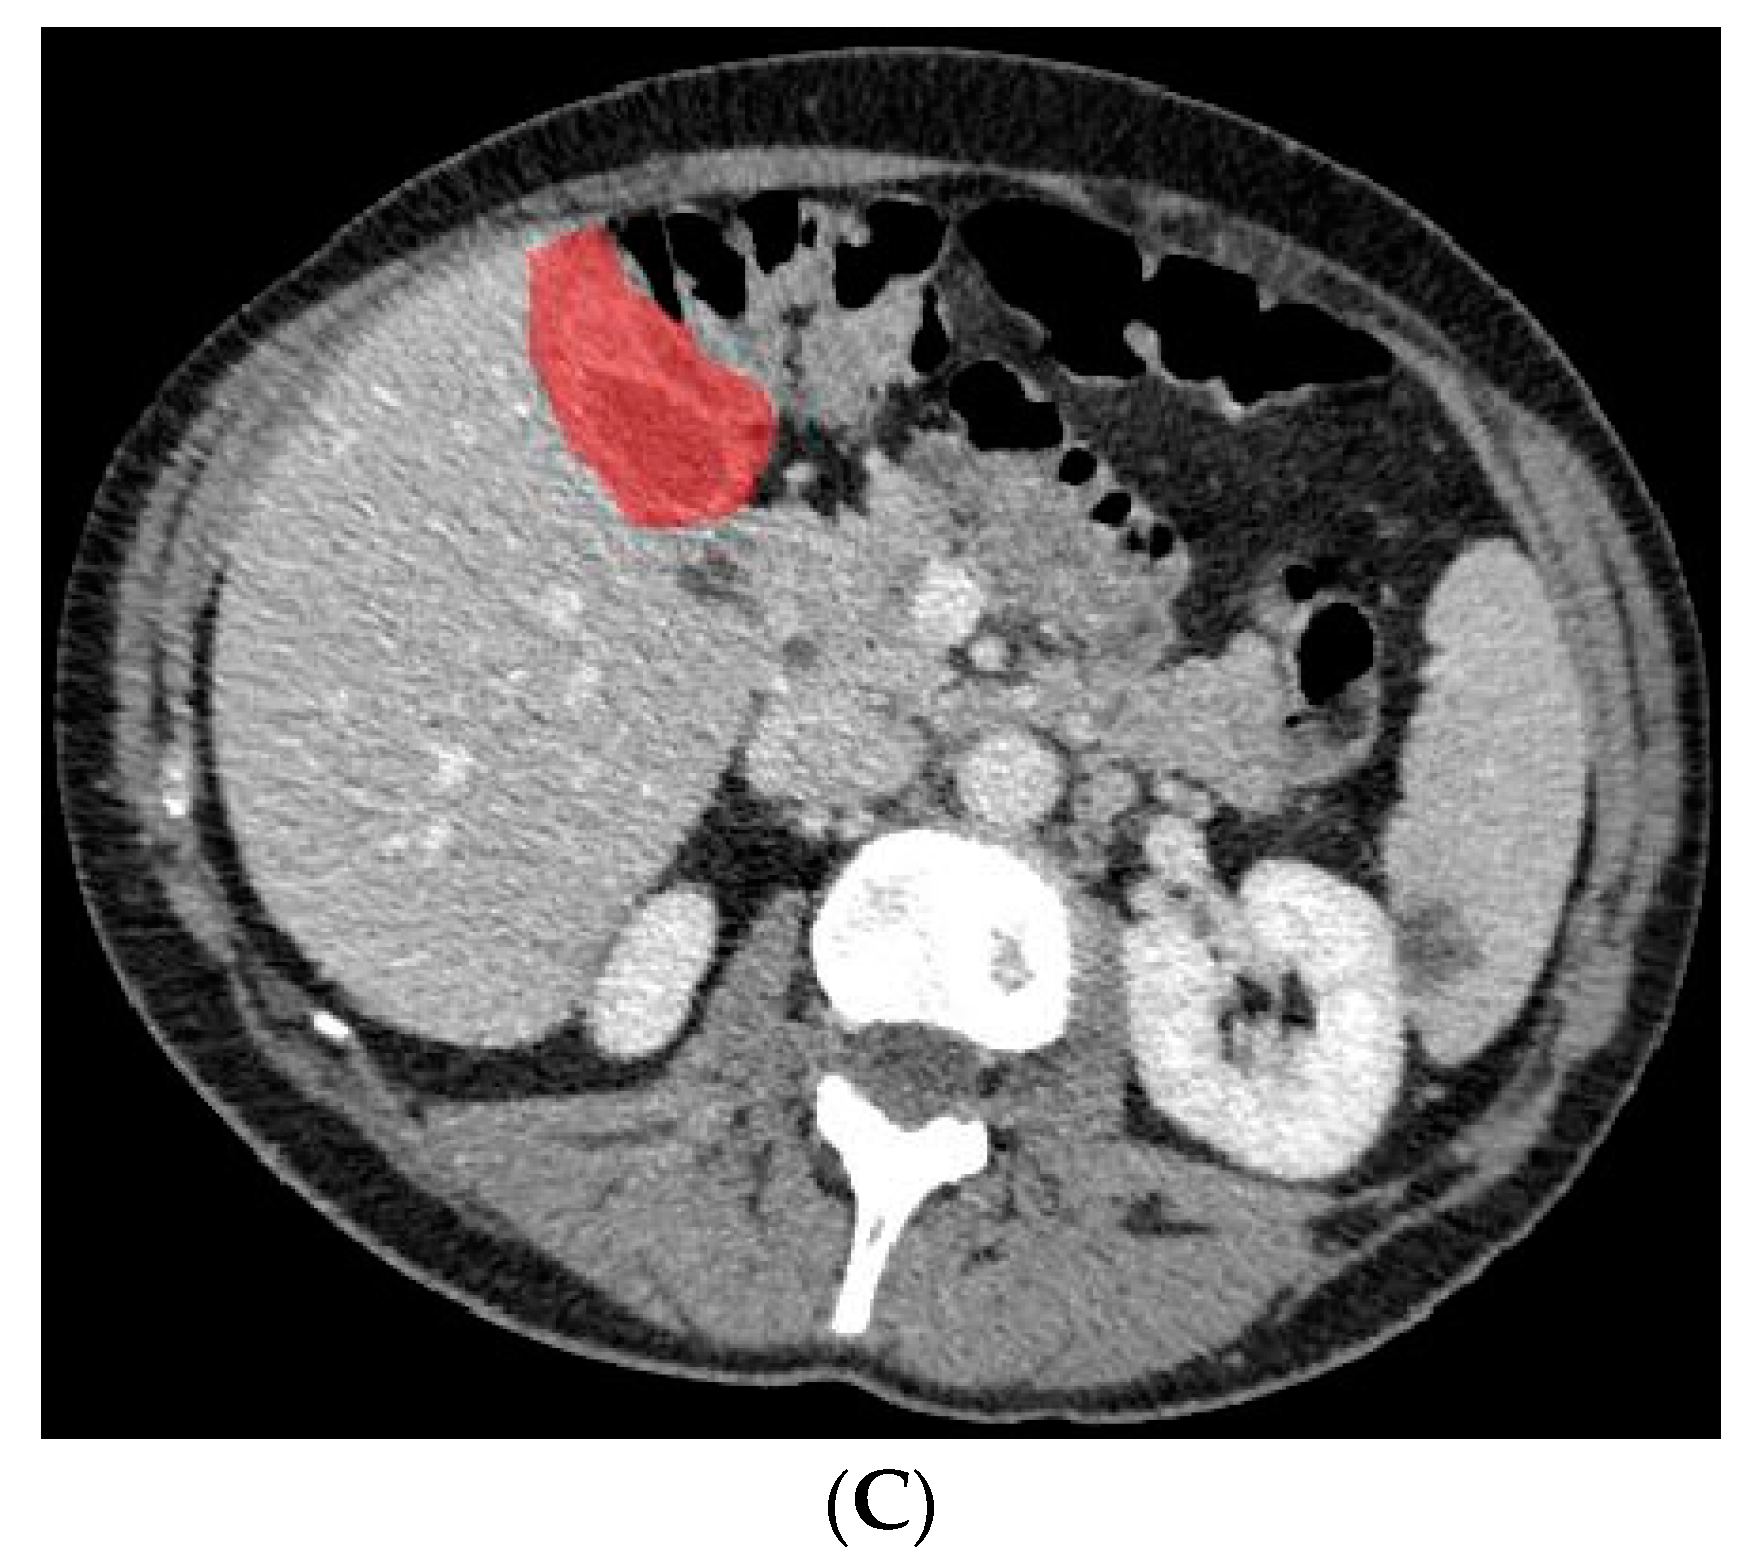

Figure 3.

Axial CT slice (A) with an example of benign gallbladder disease (adenomyomatosis, encircled in (B)) and subsequent segmented gallbladder (C).